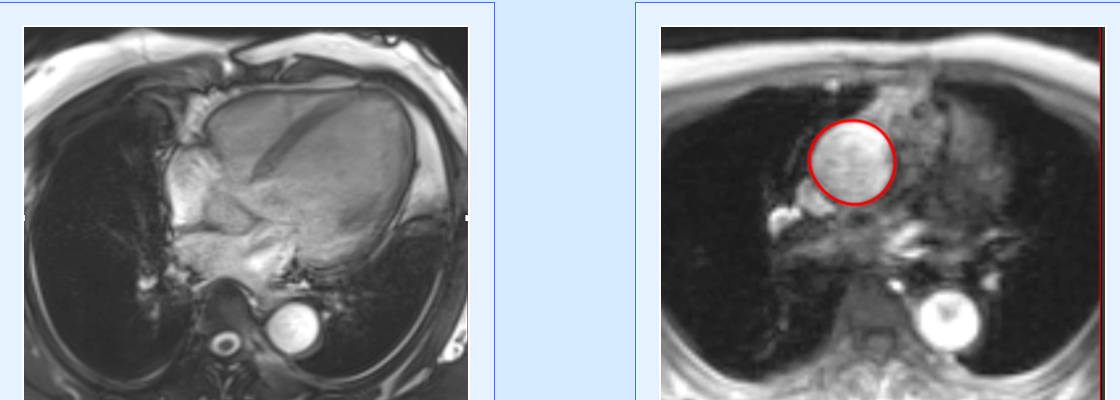

Cardiac MRI does not show vegetations, easily especially if small. However, evaluating the transaxials through the valve may help pick up small nodules and to rule out mimics.